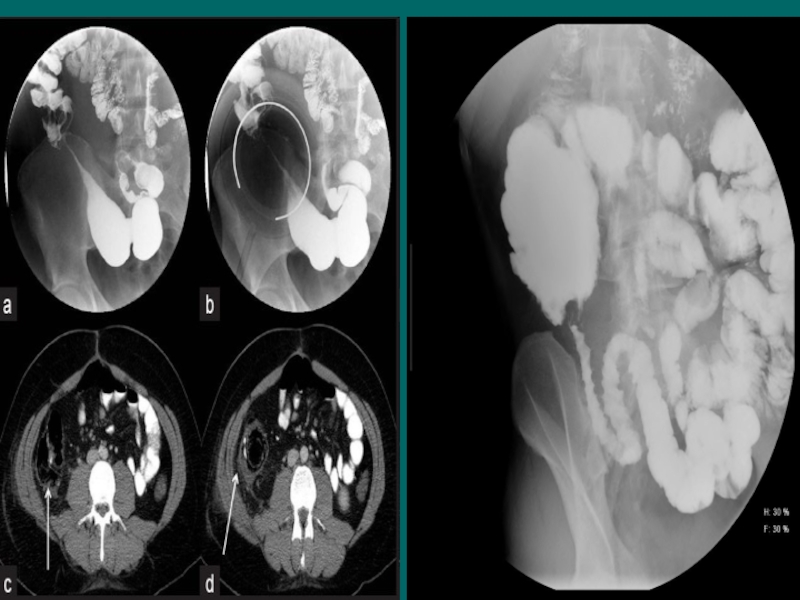

Слайд 29Рентгенологическая картина

Рентгенологическая картина